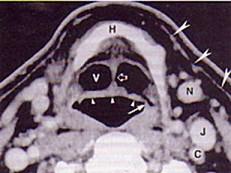

男,55岁,声嘶6年,有长期吸烟史。检查:无呼吸困难。喉镜检查:声带慢性充血,可见右侧声带可见菜花样新生物,右侧声带活动固定,喉部CT检查如下图:诊断...

问题 男,55岁,声嘶6年,有长期吸烟史。检查:无呼吸困难。喉镜检查:声带慢性充血,可见右侧声带可见菜花样新生物,右侧声带活动固定,喉部CT检查如下图: 诊断首先考虑 ( )

选项 A、喉乳头状瘤 B、喉结核 C、慢性喉炎 D、喉癌 E、声带白斑

答案 D